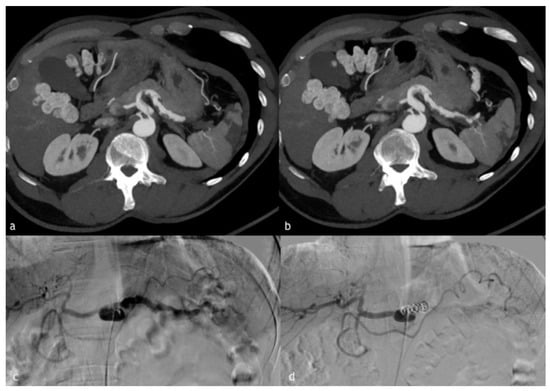

Figure 2. (ad). A 20-year-old man presented to our emergency department after high blunt trauma. (a,b) Axial and coronal MPR reconstruction images demonstrate splenic artery PSA, rounded by coarse hematoma (circle). (c) Digital subtraction angiography of splenic artery demonstrates PSA (arrow) with the presence of multiple wall irregularities, such as blebs (a warning sign of an impending breakout). (d) Post-embolization angiographic control with complete embolization of the splenic artery. There are also other coils due to another adrenal hemorrhage, successfully treated in the same session.